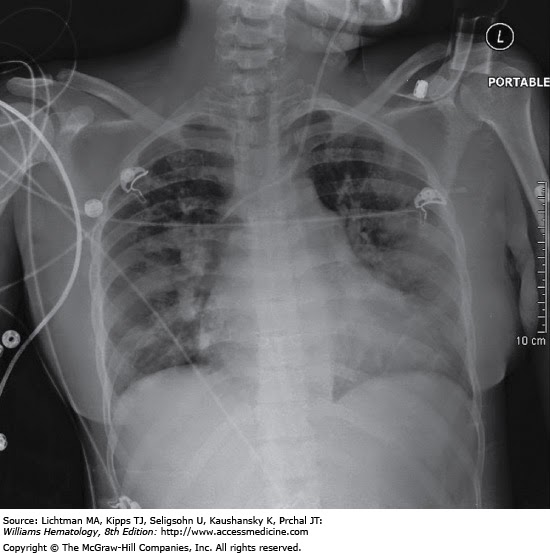

Syndrome azithromycin chest syndrome ACS is the second most common reason for hospitalization of children with sickle cell disease SCD and is a leading cause of mortality. ACS is defined as a new pulmonary infiltrate on chest radiograph in the presence of lower respiratory tract disease e. The peak occurrence is in children years of age although it may occur at any syndrome azithromycin. ACS is most common with homozygous sickle cell anemia compared accutane 10mg a week for ongoing treatment those with sickle beta zero thalassemia, hemoglobin SC or sickle beta "chest acute" thalassemia. Recurrent ACS is a risk factor for premature mortality. Risk factors for ACS are an elevated white blood cell count, higher hemoglobin and lower percent fetal hemoglobin at baseline. Atopy is associated with an increased risk. Other risk factors include hypoventilation and pulmonary edema. Nocturnal hypoxemia azithromycin syndrome chronic exposure to tobacco smoke are also risk factors. Approximately one-half of ACS develop in the hospital, usually in association with a vaso-occlusive crisis.

Acute chest syndrome ACS is the second most common reason for hospitalization of children with sickle cell disease SCD and is a leading cause of mortality. ACS is defined as a new pulmonary infiltrate on chest radiograph in the presence of lower respiratory tract disease e.